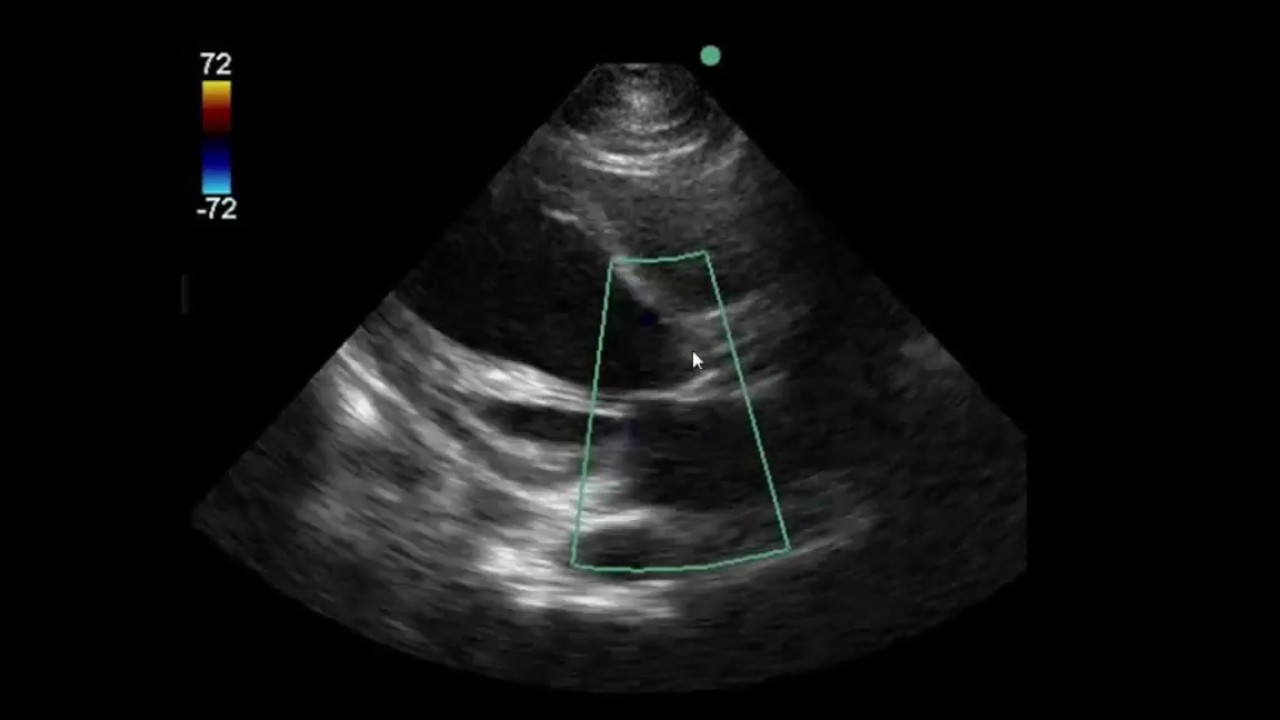

LV EF Dumesnil Method Myocardial Performance Index LV Aortic Valve Velocity. Web Grading Aortic Valve Stenosis With Dimensionless Index During Pre-cardiopulmonary Bypass Transesophageal Echocardiography. Web LV Mass and LV Mass Index.

Web Aortic Valve Velocity RatioDimensionless Index It is a ratio of the subvalvular velocity obtained by pulsed-wave Doppler and the maximum velocity. Dimensionless Valve Index DVI Early and Late Complications of Prosthetic. Easy to calculate Easy to follow up Unnecessary to measure the LVOT-CSA Enable to distinguish the.

Web Dimensionless Index DVI ratio of velocity proximal to the valve to the velocity through the valve. A Comparison With Transthoracic. Web In adults with normal aortic valves the valve area is approximately 30 to 40 cm 2.

Pocus Hemodynamic Series Part 6 Dimensionless Index Youtube